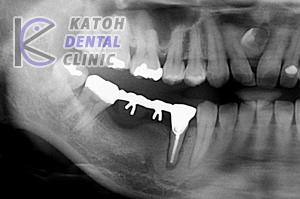

右下4567番のブリッジを長く使っていたのですが、過重負担のために4番を抜くことになりました。3本欠損の長いブリッジを新たに作る場合は保険外治療となります。予後も考え、インプラントをお薦めしました。 |

骨が吸収していて6ミリのインプラントを1本使いました。治癒を待つ間は義歯を使います。

短いインプラントを使ったので連結ブリッジで完成です。

完成後4年経過しています。プラスチックの着色が気になってきました。